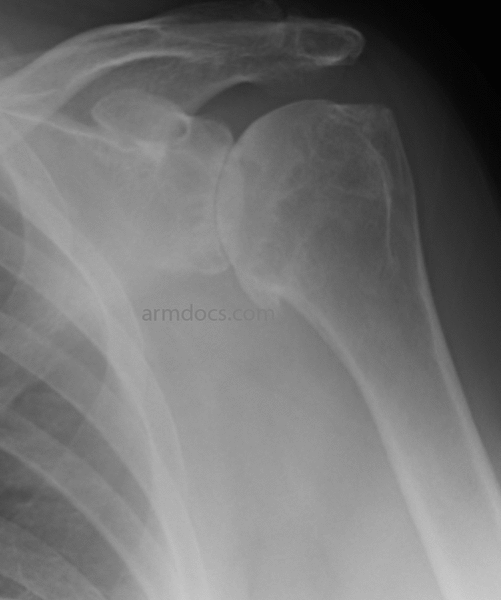

From www.armdocs.com

Shoulder Arthritis Arm Docs Arthritis In Shoulder And Arm Symptoms Bad posture or working habits, such as slouching at your desk, can make your shoulder problems worse. They range from very small injuries in the cartilage on one. It also examines how doctors diagnose and treat shoulder arthritis and includes tips for. Symptoms of shoulder arthritis may include pain in the shoulder joint, stiffness and reduced range of motion. As. Arthritis In Shoulder And Arm Symptoms.